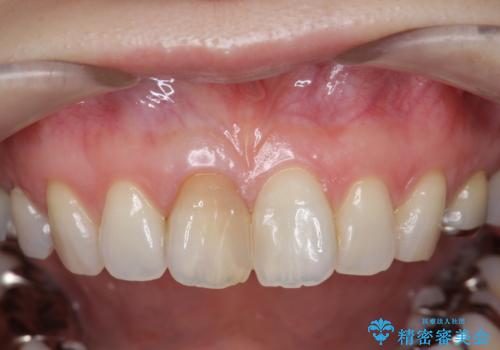

前歯の変色 セラミック審美補綴

- 前歯の変色の改善を希望され来院されました.

以前に神経が死に、根管治療を行った歯の変色が認められたためセラミックによる審美補綴治療を計画します。

神経治療を行い補綴(かぶせもの)治療を行わないと、変色が目立ち審美障害を起こすことがあります。

このような場合、セラミックによる審美改善が治療の一案として提案されます。